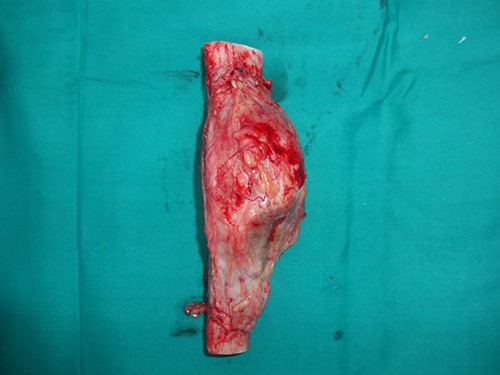

A 33-year-old gentleman presented with slow-growing swelling over the anteromedial aspect of the midshaft of left leg with dull aching pain for 2 years. The swelling was bony hard, 10 cm long and was fixed to the underlying tibia (Fig. 1). Anterior and posterior tibial arteries, sensory and motor functions of the affected legs were intact. Preoperative incisional biopsy report shows multiple epithelial-like cells in a background of fibrous dysplasia, suggestive of adamantinoma. X-ray suggested lytic expansile lesion with multiple septa and sclerotic margins involving the tibia’s diaphysis (Fig. 2). Computed tomography scan showed a cystic expansile lesion with a sclerotic margin obliterating the medullary cavity. Chest X-ray and abdominal ultrasound were normal. The bony defect in the tibia after wide excision of the tumour was 16 cm (Fig. 3) reconstructed with free fibula flap harvested from the opposite leg (Fig. 4). The bone flap was fixed to the tibia with a dynamic compression plate and bicortical screws (Fig. 4). The fibula flap pedicle, peroneal artery and one venae comitantes were anastomosed with the posterior tibial artery and great saphenous vein, respectively. Post-operatively, the flap, flap donor site and recipient’s leg wound healed without complications. Histopathological examination of excised lesion confirmed the diagnosis of classic adamantinoma with margins free of tumour (Fig. 5). After 1 year, there was radiological bone union, evidenced by uninterrupted bony borders between the fibula and recipient tibia bone, obscured osteotomy line at both the junctions and hypertrophy of the transferred fibula as per the bone union criteria by Hsu et al. [3]. The patient started partial weight-bearing in the operated limb after 6 months without any displacement or fracture of the vascularized bone graft. Three years post-surgery follow-up showed good evidence of bony integration and hypertrophy of the bone of the fibula flap, gradually accepting the shape of the tibia without any local recurrence or distant metastasis (Fig. 6). Patient is completely bearing weight on the affected lower limb with good function (Fig. 7).

Intraoperative image with bone defect bridged with vascularized free fibula fixed with dynamic compression plate.